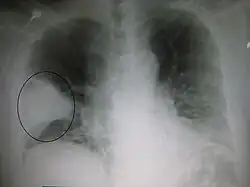

Chest film showing increased opacity in both lungs, indicative of pneumonia -